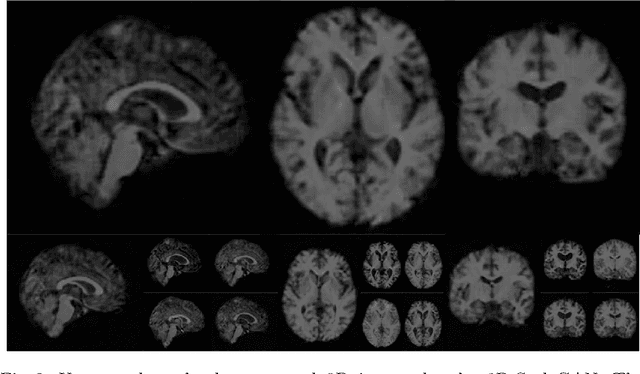

Abstract:Image synthesis via Generative Adversarial Networks (GANs) of three-dimensional (3D) medical images has great potential that can be extended to many medical applications, such as, image enhancement and disease progression modeling. However, current GAN technologies for 3D medical image synthesis need to be significantly improved to be readily adapted to real-world medical problems. In this paper, we extend the state-of-the-art StyleGAN2 model, which natively works with two-dimensional images, to enable 3D image synthesis. In addition to the image synthesis, we investigate the controllability and interpretability of the 3D-StyleGAN via style vectors inherited form the original StyleGAN2 that are highly suitable for medical applications: (i) the latent space projection and reconstruction of unseen real images, and (ii) style mixing. We demonstrate the 3D-StyleGAN's performance and feasibility with ~12,000 three-dimensional full brain MR T1 images, although it can be applied to any 3D volumetric images. Furthermore, we explore different configurations of hyperparameters to investigate potential improvement of the image synthesis with larger networks. The codes and pre-trained networks are available online: https://github.com/sh4174/3DStyleGAN.